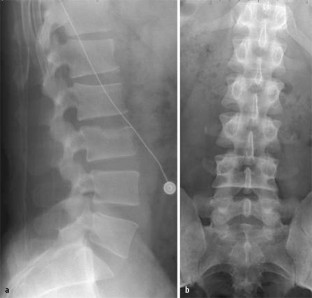

Abb. 2